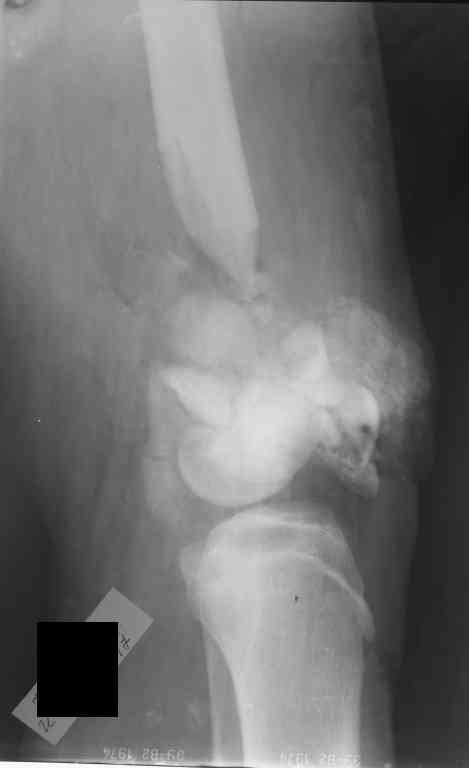

Внутрисуставной перелом бедренной кости

Уважаемые коллеги! Хотелось бы услышать ваше мнение по тактике лечения перелома бедра.

Пациент 17 лет. Травма 07.10.2006 - попал под грузовик. Рана на бедре зажила первичным натяжением. Мы рассматриваем следующие варианты: открытая репозиция + 1)остеосинтез аппаратом внешней фиксации; или 2)фиксация пластиной LCP. Ваши предложения? Как бы вы поступили с имеющимся дефектом бедренной кости?Екатерина Анатольевна Озерова

Картинка конечно страшненькая, но можно рискнуть и не открываться.

Внешняяя фиксация тем и хороша, что позволяет получать нормальные ФУНКЦИОНАЛЬНЫЕ результаты при жуткой анатомии. Попробуйте собрать закрыто. Адаптация возможна постепенная. Важно суставные поверхности сохранить конгруетными. постепенно загоните"шип" проксимального отломка в ценр мышелков и на фиксацию.